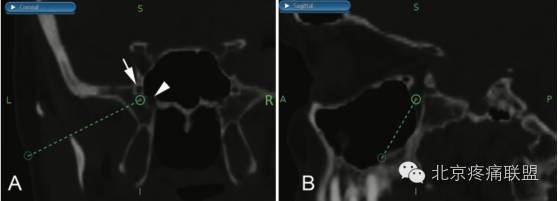

手术过程:将CT扫描图像上传到StealthStation S7系统(美敦力),并标示出圆孔与翼管之间的区域,该区域即为SPG的所在位置。进针点选在颧弓下方,以避过下颌骨的冠突(图1)。

1  翼颚窝的冠状位(A)和矢状位(BCT扫描影像。

注:靶点(浓绿色圆圈)位于圆孔(箭标)和翼管(箭头)之间。浅绿色圆圈为穿刺点,虚线为设计的穿刺路径。